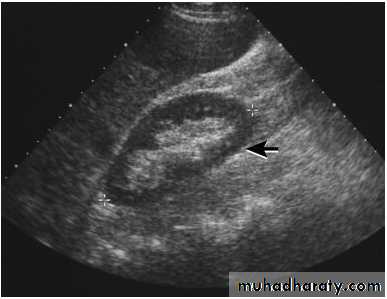

Renal ultrasound is a simple noninvasive examination .The kidney is bean shaped and has bright central echoes because of the fat surrounding the collecting system.

Normal renal ultrasound.

A longitudinal view of the right kidney was obtained by passing the sound beam through the right lobe of the liver. The kidney is seen behind this, outlined by the markers. The central bright echoes in the kidney are due to fat around the collecting system.